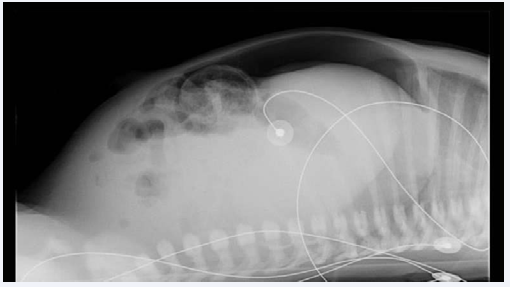

Despite nasogastric tube decompression, cessation of feeding and antibiotics, on day nine of life, his condition was still not improving. Laboratory studies showed a C-reactive protein level of 16,9 mg/dL, a white blood cell count of 13,77 x 103/μL and a hypoalbuminemia of 29,8 g/L (normal values: 34 – 42g/L). Abdominal plain x-ray was repeated and revealed an image of free intra-peritoneal air (Figure 2).

Figure 2 Abdominal plain x-ray repeated on day nine revealing an image of free intra-peritoneal air that lead to referral to a pediatric surgical center.